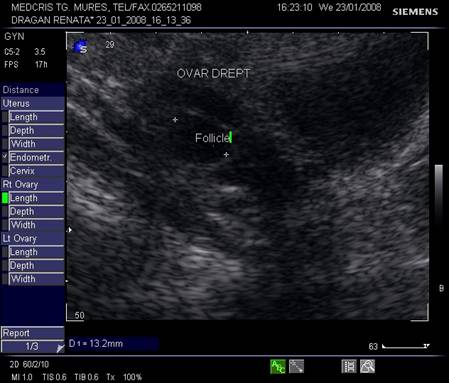

Ovarele. Sectiunea longitudinala directa, spre peretele lateral pelvin, la ecografia transvaginala, pune in evidenta ovarele cu forma elipsoidala. Acestea au structura ecografica relativ slab ecogena, in apropierea si sub vasele iliace.[5]

La pacientele care nu consuma contraceptive hormonale orale se pot identifica usor foliculii selectati preovulator sau corpul galben.

Dupa ziua a 5-7, un folicul ovarian devine dominant , fata de ceilalti ce devin atretici. In ziua 10 -a - 11-a foliculul depaseste 12 mm diametru. Cresterea foliculara de 2 - 3 mm/zi ne duce la un folicul preovulator de cca 21 mm diametru (24 - 26 mm). Doi foliculi dominanti au fost identificati in 10% din ciclurile spontane [8].

Deoarece foliculii sunt ovoidali, diametrul mediu conteaza pentru foliculometria, dupa masurarea a 3 diametre si impartirea la 3.[6]

Fig. nr.371. Folicul selectat ziua a XI a de ciclu menstrual, la ecografia transvaginala